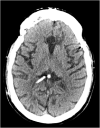

Complications related to Ventriculoperitoneal shunt placement are common, and multiple. Among them blockage and infection. We report a case of 44 years old man admitted to our hospital after an obstruction of his ventriculo-peritoneal shunt by an air bubble that caused behavioral problems and confusion. The patient was operated twice, the last time the puncture point had to be changed. The follow up was marked by a clear clinical improvement. Shunt malfunction continues to be a common neurosurgical problem in patients with shunted hydrocephalus, often leading to frequent and sometimes lengthy hospital stays. This case illustrates the management of this rare situation causing air bubble shunt obstruction.